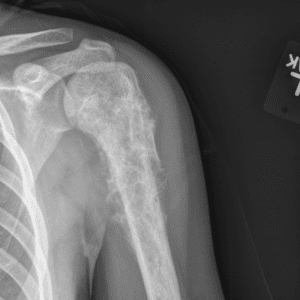

Pediatric Radiographs